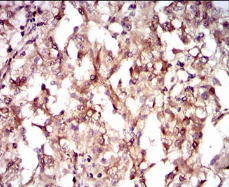

IHC    1/200 - 1/1000